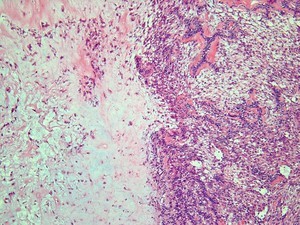

A 34 year old woman was recently in a car accident where she sustained severe trauma. She underwent surgery and had to recieve 3 units of blood. A week later during her hospital stay she reports horrible abdominal pain and begins to vomit- the vomit contains threads of blood. Based on the histologic specimen below, what is her diagnosis and what caused this? What is the treatment?

Acute erosive/hemorrhagic gastritis= Abrupt onset of ab pain & bleeding a/w ETOH, NSAIDs, or low hemodynamic state following trauma

Mechanism: Breakdown of mucosal barrier due to:

Etiologies:

Treatment: Acid-suppression (H2 blockers, PPIs)